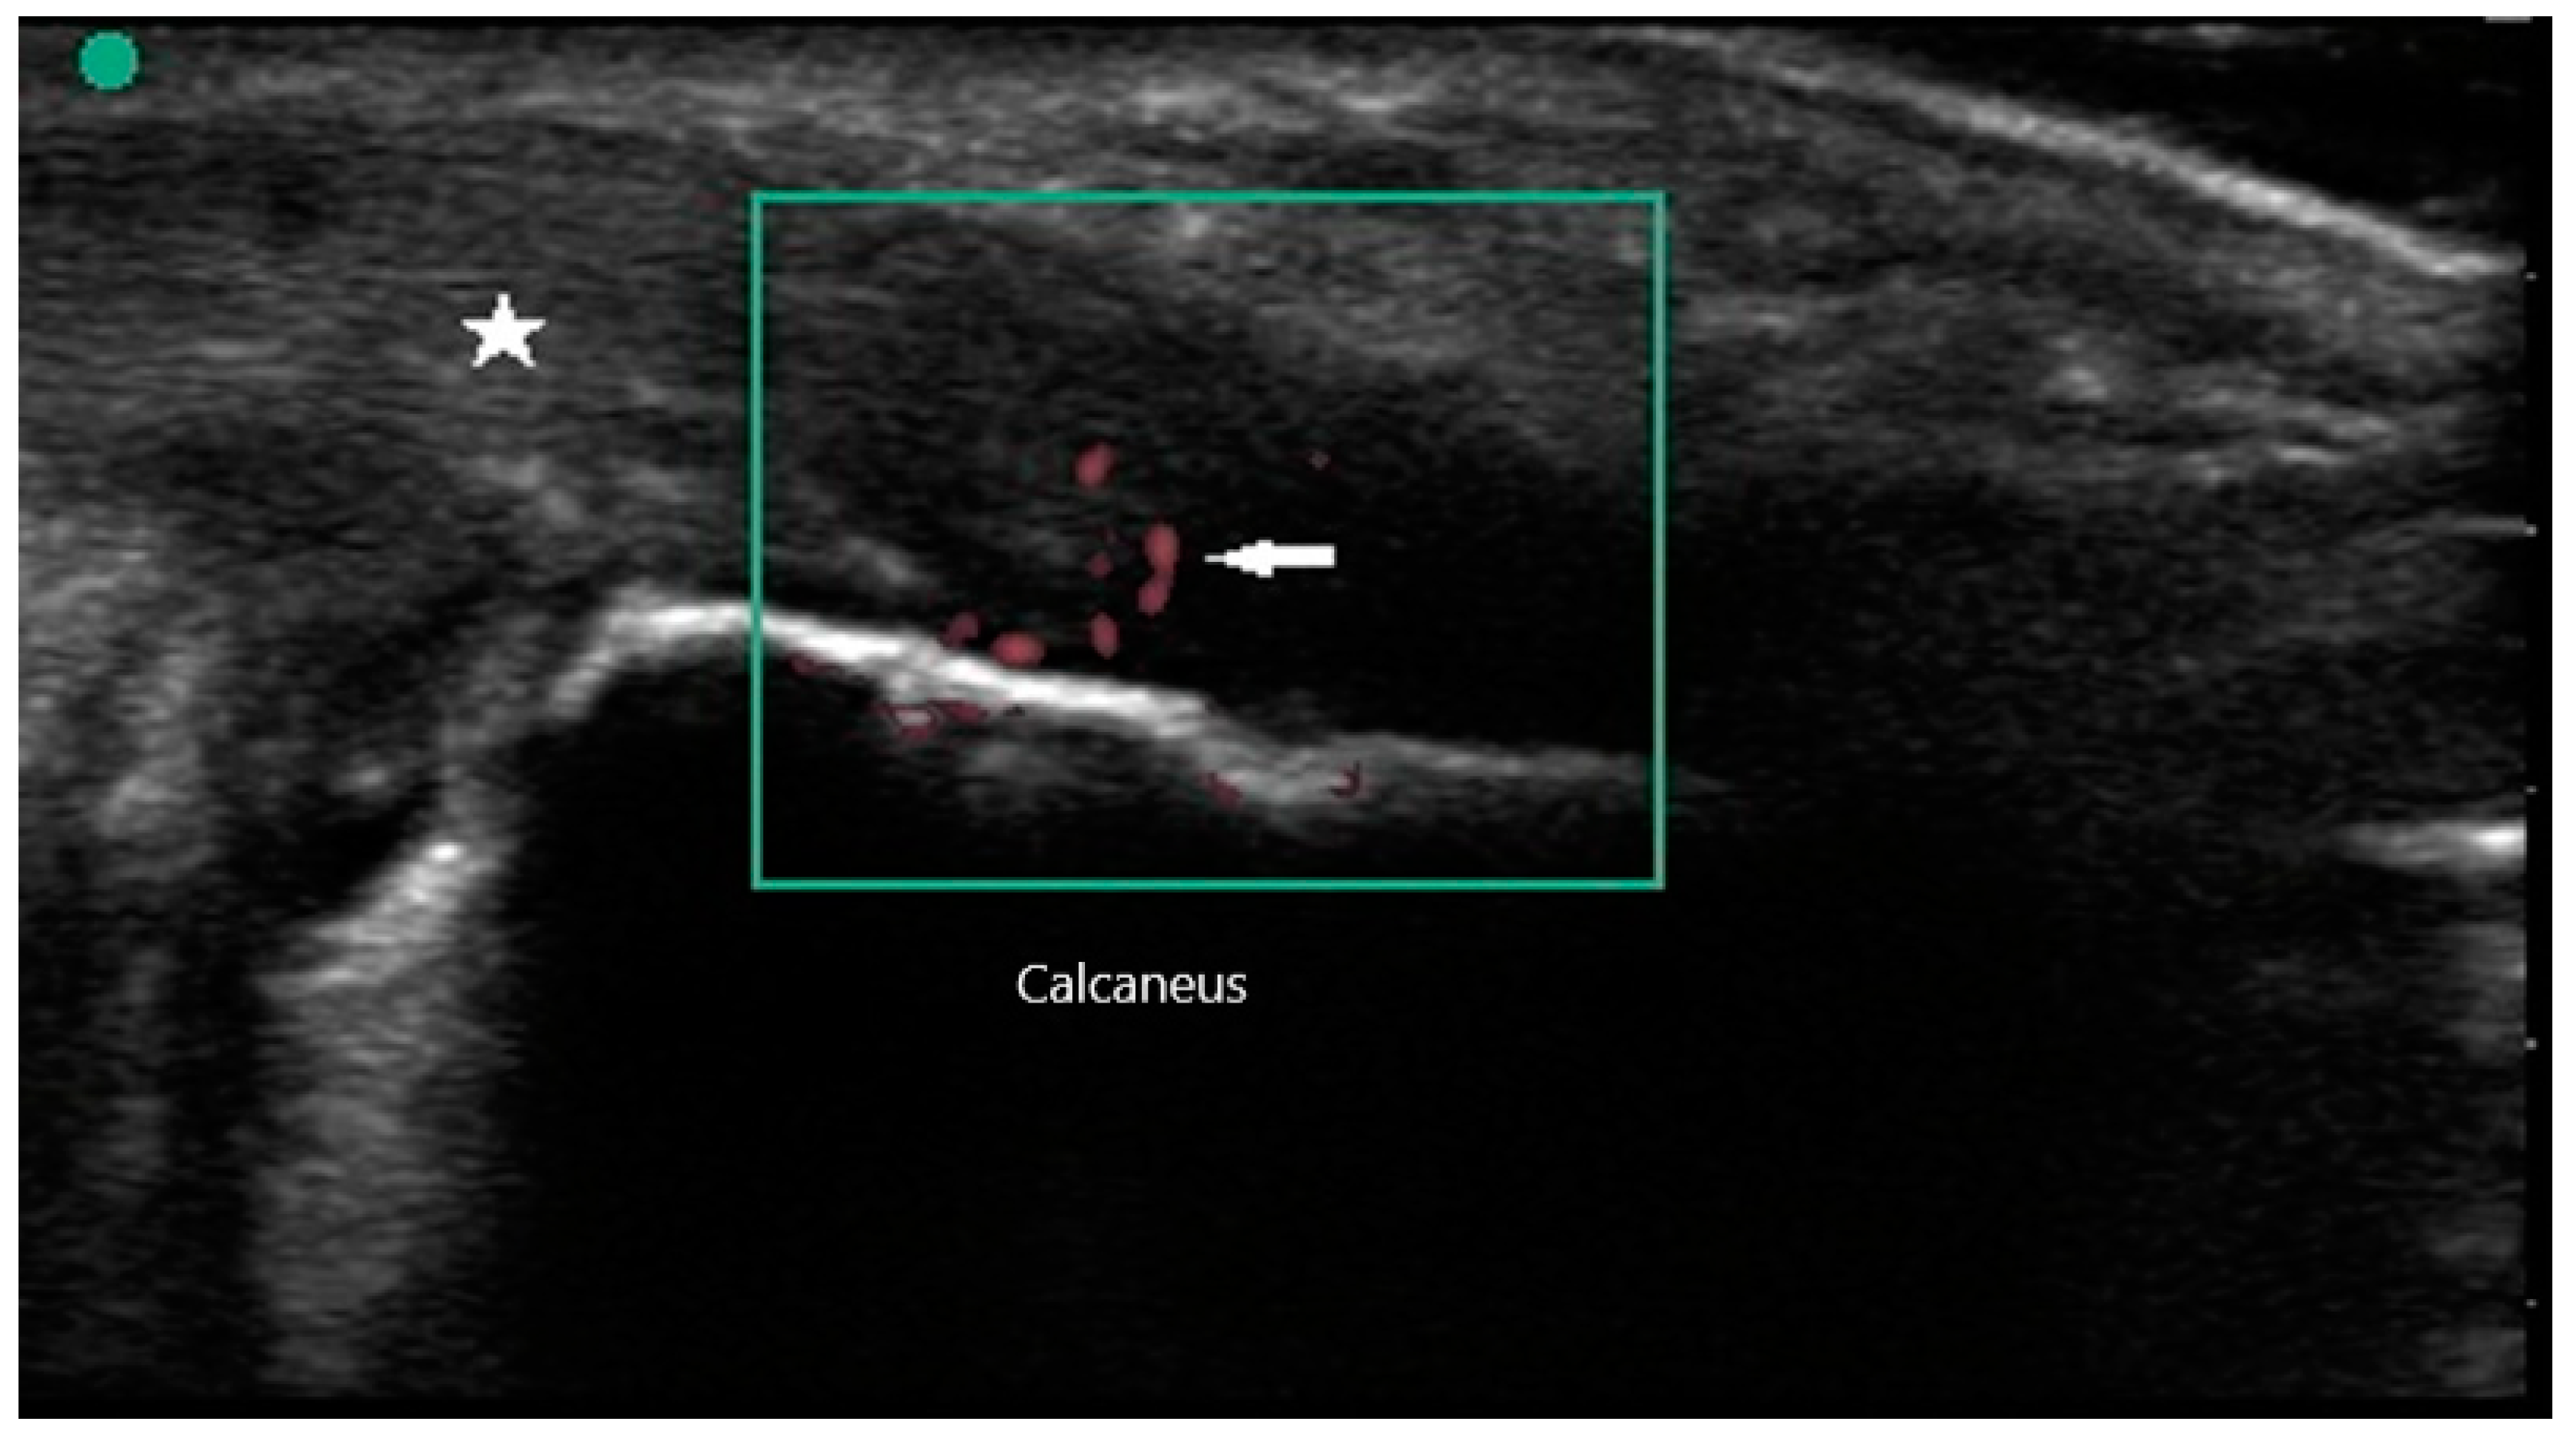

Peripheral joint involvement can be similar between SpA and RA, though the former more commonly presents as asymmetric oligo-arthritis. SpA, especially psoriatic arthritis, may also affect the DIP joints, which is a feature never seen in RA. Furthermore, tendinous and peritendinous structures are more often affected, as is seen in dactylitis and enthesitis. Sonographic characteristics of peripheral joint inflammation in SpA are also similar to that of RA, both in greyscale and power Doppler (Figure 5). Joint effusions are compressible, displaceable, and hypoechoic substances within the joint space, while synovitis is a non-compressible, non-displaceable thickening of the synovium. Hyperemia on power Doppler may also be present. Enthesitis is inflammation of the insertion of ligament, fascia, or tendon into bone. The most commonly affected entheses are the Achilles tendon (Figure 6), plantar fascia, lateral humeral epicondyle, greater trochanter, and pes anserinus [30]. On physical examination, patients may exhibit pain on palpation or swelling of these structures. Sonographic findings reveal hypoechoic or thickened insertion of the tendon 2 mm or less from the bony cortex. Doppler signal, bone spurs at tendinous insertion known as enthesophytes, calcifications, or erosions may be present [31]. Dactylitis, or “sausage” digits (Figure 7), is a well described yet rare finding in SpA, characterized by diffuse tenosynovitis, synovitis, and enthesitis [32].

Figure 6. Enthesitis of Achilles tendon (star) with power Doppler signal (arrow).